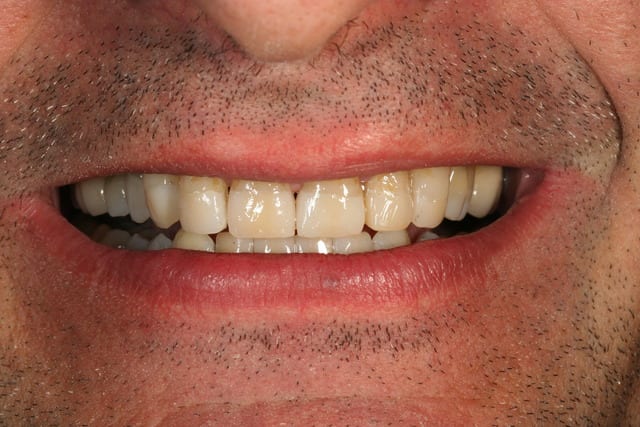

ça aura été une longue journée, pas eu le temps de peaufiner occlusion ou de polir partout bien comme il faut, j'y reviendrais

première impression sympa pour le grand changement

les points de contacts étaient bon, et j'ai pu en retoucher 3 en adjonction pour avoir un truc bien partout

par contre niveau occlusion des dents haut/bas, je suis moins sur, je pense qu'on aurait pu faire mieux, je pourrais regarder tranquillement quand il reviendra, et éventuellement ajuster un peu si besoin

Mr t sourire vcriu0 - Eugenol